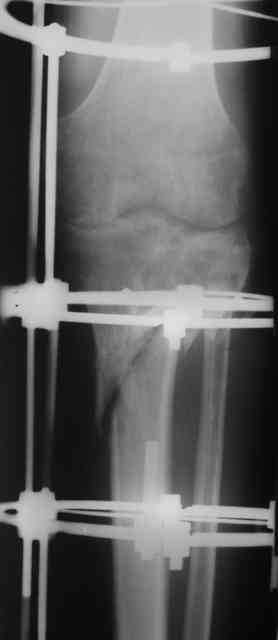

Р-граммы и фото за 4.05.2007 - 7-е сутки после операции.

Ход операции - линейным разрезом по передней поверхности голени обнажена зона ложного сустава большеберцовой кости. От кости отсепарованы медиально м/ткани. Из зоны ложного сустава убраны рубцовые ткани, мобилизован дистальный отломок. По передней поверхности удалены два осколка, связанных грануляциями. Произведено удаление грануляционной ткани из проксимального отломка (на вид сине-серого цвета), "чистого" гноя не было. Затем произведено наложение аппарата и репозиция отломков. По передне-медиальной поверхности образовался дефект до 4х2х2 см + полость в проксимальном отломке. Удаленные осколки очищены от грануляций, уложены в место дефекта, зажаты между отломками. После иссечения раны по передней поверхности, находящейся рядом с операционной раной, последняя ушита с большим натяжением.

Перелом мыщелка сросся. Проксимальный отломок очень порозный.

На перевязках - из раны небольшое кол-во сукровичного отделяемого. Отек голени умеренный, состояние кожи на фото.

Аппарат видел, репозиции не заметил. О "наложенном" аппарате: спицы в проксимальном отломке б\берцовой кости проведены очень низко, и опять только две, как и в первом аппарате. Почему только одна спица в дистальном парафрактурном кольце? Проксимальная база на бедре должна улучшить стабильность проксимального фрагмента tibia? Ничего подобного двумя спицами в одной базе при таком длинном рычаге вы не добьетесь, а вот совсем потерять движения в коленном суставе они почти гарантируют.

О репозиции: мыщелок сросся и слава Богу, но основные отломки фиксированы в вальгусном положении, собственно как и было, это критично. В чем состояла репозиция?

Согласен с оценкой Алексея. Секцию на бедро не нужно, на ровном месте сформируется контрактура коленного сустава. В проксимальный эпиметафиза большеберцовой ввели бы 4-5 спиц с упорами, в том числе в виде петли, и хватило бы.